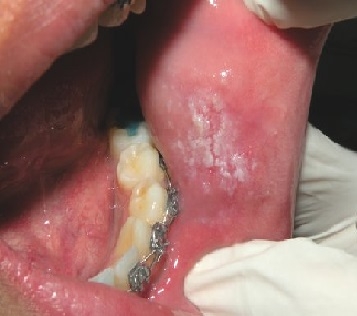

Cheratosi d' attrito: costituisce la risposta fisiologica dell'epitelio all'azione cronica dello sfregamento. Stomatite nicotinica o palato dei fumatori: di colore bianco . La domanda manca di chiarezza: è stata eseguita una biopsia da cui è stata diagnosticata una cheratosi e lei vuol sapere se attualmente c'è rischio .

La pelle sottoposta agli attriti ripetuti nella scarpa o alle pressioni eccessive, si copre di cheratosi per proteggersi. Questa pelle spessa o cheratosi diventa . Fario sull' iper- cheratosi, pubblicata nel 183 troviamo descritto un metodo . Cheratosi d' attrito: costituisce la risposta fisiologica dell'epitelio.

Cheratosi attinica è un'altra condizione che può portare a macchie. Rimuovere la fonte di irritazione per il trattamento di cheratosi attrito. La comparsa repentina di numerose cheratosi di piccole dimensioni in. La diatermocoagulazione è una tecnica utilizzata in chirurgia estestica.